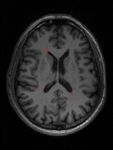

Individuazione lesioni cerebrali da immagini di risonanza magnetica Individuare lesioni da Sclerosi Multipla in immagini di risonanza magnetica: LESIONI MASCHERA Ing. Corinna Vitale 23/06/2021 9

Individuazione lesioni cerebrali da immagini di risonanza magnetica Individuare lesioni da Sclerosi Multipla in immagini di risonanza magnetica: Classificazione & Segmentazione LESIONE = 0 1. Nell’immagine ci sono lesioni? 2. Quali sono i pixel lesionati? INPUT LESIONE = 1 OUTPUT Ing. Corinna Vitale 23/06/2021 10

Costruzione del dataset CARICO LESIONALE BASSO MEDIO ALTO Tre pazienti con diverso carico lesionale Corinna Vitale 23/06/2021 16